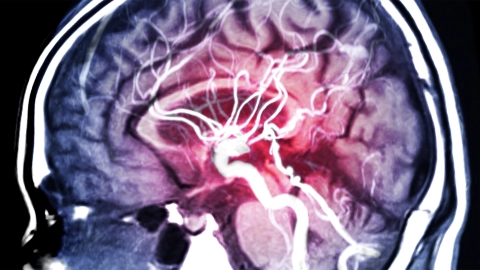

Ein EEG-Monitor zeigt das Bild eines gescanntes Schädels, durch den Nervenbahnen verlaufen. Im Hintergrund sitzt ein Mann auf einem Arztstuhl. Er hat seinen Kopf leicht nach hinten an die Lehne geneigt und scheint seine Aufen geschlossen zu haben.

Bildschirm mit Bildern eines gescannten Schädels und Gehirns. Bildschirm mit Bildern eines gescannten Schädels und Gehirns.

Schlaganfall

Bei einem Schlaganfall wird ein Teil des Gehirns nicht mehr richtig durchblutet. Das kann lebensbedrohlich sein. Um schweren Folgen vorzubeugen, ist eine rasche Behandlung wichtig.

Menschliches Gehirn im Querschnitt: Blutgefäße und Hirnschlagader sind sichtbar. Menschliches Gehirn im Querschnitt: Blutgefäße und Hirnschlagader sind sichtbar.

Hirnaneurysma

Ein Hirnaneurysma ist eine Ausbuchtung einer Schlagader im Gehirn. Oft bleibt das unbemerkt und ohne Beschwerden. Reißt das Aneurysma, kommt es zu einer lebensbedrohlichen Hirnblutung.